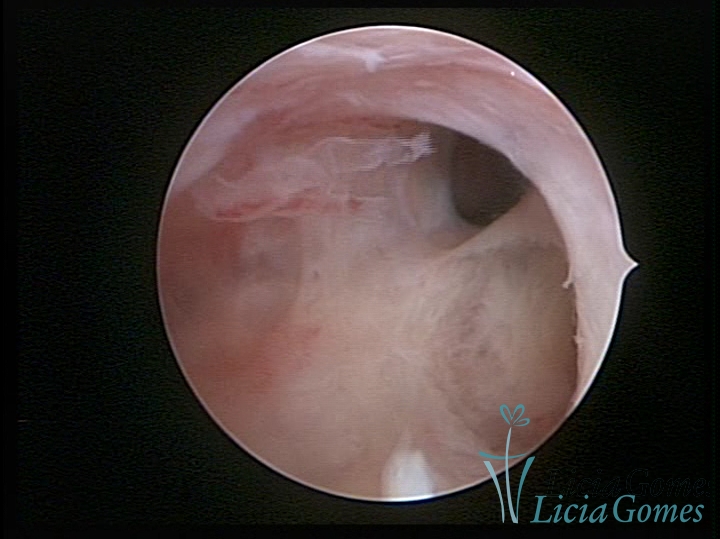

FIBROUS SYNECHIA

Uterine synechiae are scars (adherence) between the surface of the uterine walls, which may occur after the surgical procedure, uterine curettage, or after an inflammatory process in the uterine cavity (endometritis), which may lead to menstrual changes, infertility and obstetric complication such as abortion and premature birth.